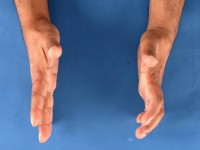

Complicaties en late gevolgen van lepraDe infectie

zelf kan met multidrug therapie worden behandeld, maar het grote probleem bij

lepra is de (meestal irreversibele)

neuropathie die

wordt veroorzaakt door de immuunreactie. De neuropathie uit zich als een verminderde

sensibiliteit in de laesies, maar later ook in perifere neuropathie, niet alleen

sensibel maar ook motorisch. De sensibiliteit voor druk kan worden getest met

filamenten die doorbuigen bij een bepaalde druk. Verdikte zenuwen kunnen worden

gepalpeerd. Voor een goed neurologisch onderzoek bij lepra is ervaring nodig.

Door de neuropathie voelt een lepra patiënt geen hitte maar ook geen pijn. Er

ontstaan wondjes aan de vingers door

heetwaterverbranding

of

trauma, en aan de tenen en voetzolen door druk

of knellende schoenen. Het voetgewelf zakt in waardoor er een bolle voet ontstaat

met nieuwe drukpunten midden onder de voet. De

ingezakte voet

wordt vaak een

Charcot voet of

rockerbottom

voet genoemd. De tenen gaan in een dwangstand staan en krijgen

nieuwe drukpunten aan de bovenkant en aan de onderkant. De

wondjes

en

drukulcera zijn vaak bedekt met een dikke laag

eelt (

callus), gaan dieper dan aan de buitenkant zichtbaar

is en kunnen infecteren en overgaan in een

osteomyelitis.

Vaak moeten tenen en vingers worden geamputeerd vanwege infectie en osteomyelitis.

![Atrofie duimmuis (click on photo to enlarge) [source: www.huidziekten.nl] Atrofie duimmuis](../../../images/neuropathie-bij-lepra-2z.jpg) |

atrofie

duimmuis |